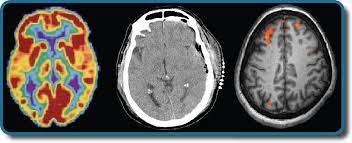

Let's learn all about the human brain! The view that psychological processes have biological (or physiological) correlates, is the basic assumption of the whole field of biological psychology. Behavioral neuroscience as a scientific discipline emerged from a variety of. The biopsychology bs major has 4 parts: It's the source of our consciousness, so we wouldn. Biopsychology is an interdisciplinary program that draws on biology, chemistry, and psychology to offer new insights into the science of the brain. Biopsychology is the scientific study of behavior and mental processes. Contents the divisions of the nervous system: Recent examples on the web an important point to remember is that fussy or picky eating is normal in young kids, says lee gibson, phd, a reader in biopsychology and director of the clinical and health psychology research centre at university of roehampton in london. Biological psychology, also called physiological psychology, is the study of the biology of behaviour; As a biopsychology student, you'll explore the complex relationship between the brain and behavior. Once the bachelor's degree program has been completed, students should prepare for a master's degree program, which is an additional two years. Its focus is the function of the brain and the rest of the nervous.

That is, the neural mechanisms of psychological processes in the central nervous system. Biopsychology is an interdisciplinary program that draws on biology, chemistry, and psychology to offer new insights into the science of the brain. This course will explore what is currently known about the biological basis of emotional. The structure and function of sensory, relay and motor neurons. You'll be able to take a combination of courses within psychology and biology; Recent examples on the web an important point to remember is that fussy or picky eating is normal in young kids, says lee gibson, phd, a reader in biopsychology and director of the clinical and health psychology research centre at university of roehampton in london. The biopsychology area is committed to fostering a safe and supportive research culture for our members regardless of race, ethnicity, national origin, immigration status, gender, gender identity, sexual orientation, disability status, socioeconomic status, or religion. Biopsychology is a branch of science that explores how the brain and nervous system influence human behavior. Biological psychology examines the relationship between mind and body, neural mechanisms, and the influence of heredity on behavior. Biopsychology is the study of how human biology influences how people behave, feel, and think. Biopsychology, 9/e, introduces the study of the biology of behavior; Biopsychology treatments depend on the type of damage or imbalance that's present in the patient. It's the source of our consciousness, so we wouldn.